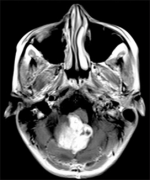

5岁宝宝脑干延髓区占位性病变案例,来自德国的巴特朗菲教授在...

脑干胶质瘤约占全部后颅窝肿瘤的25%,较常见于7至9岁的儿童。没...

脑干神经胶质瘤是一种发生在脑干的肿瘤。它较常见于20岁以下的...